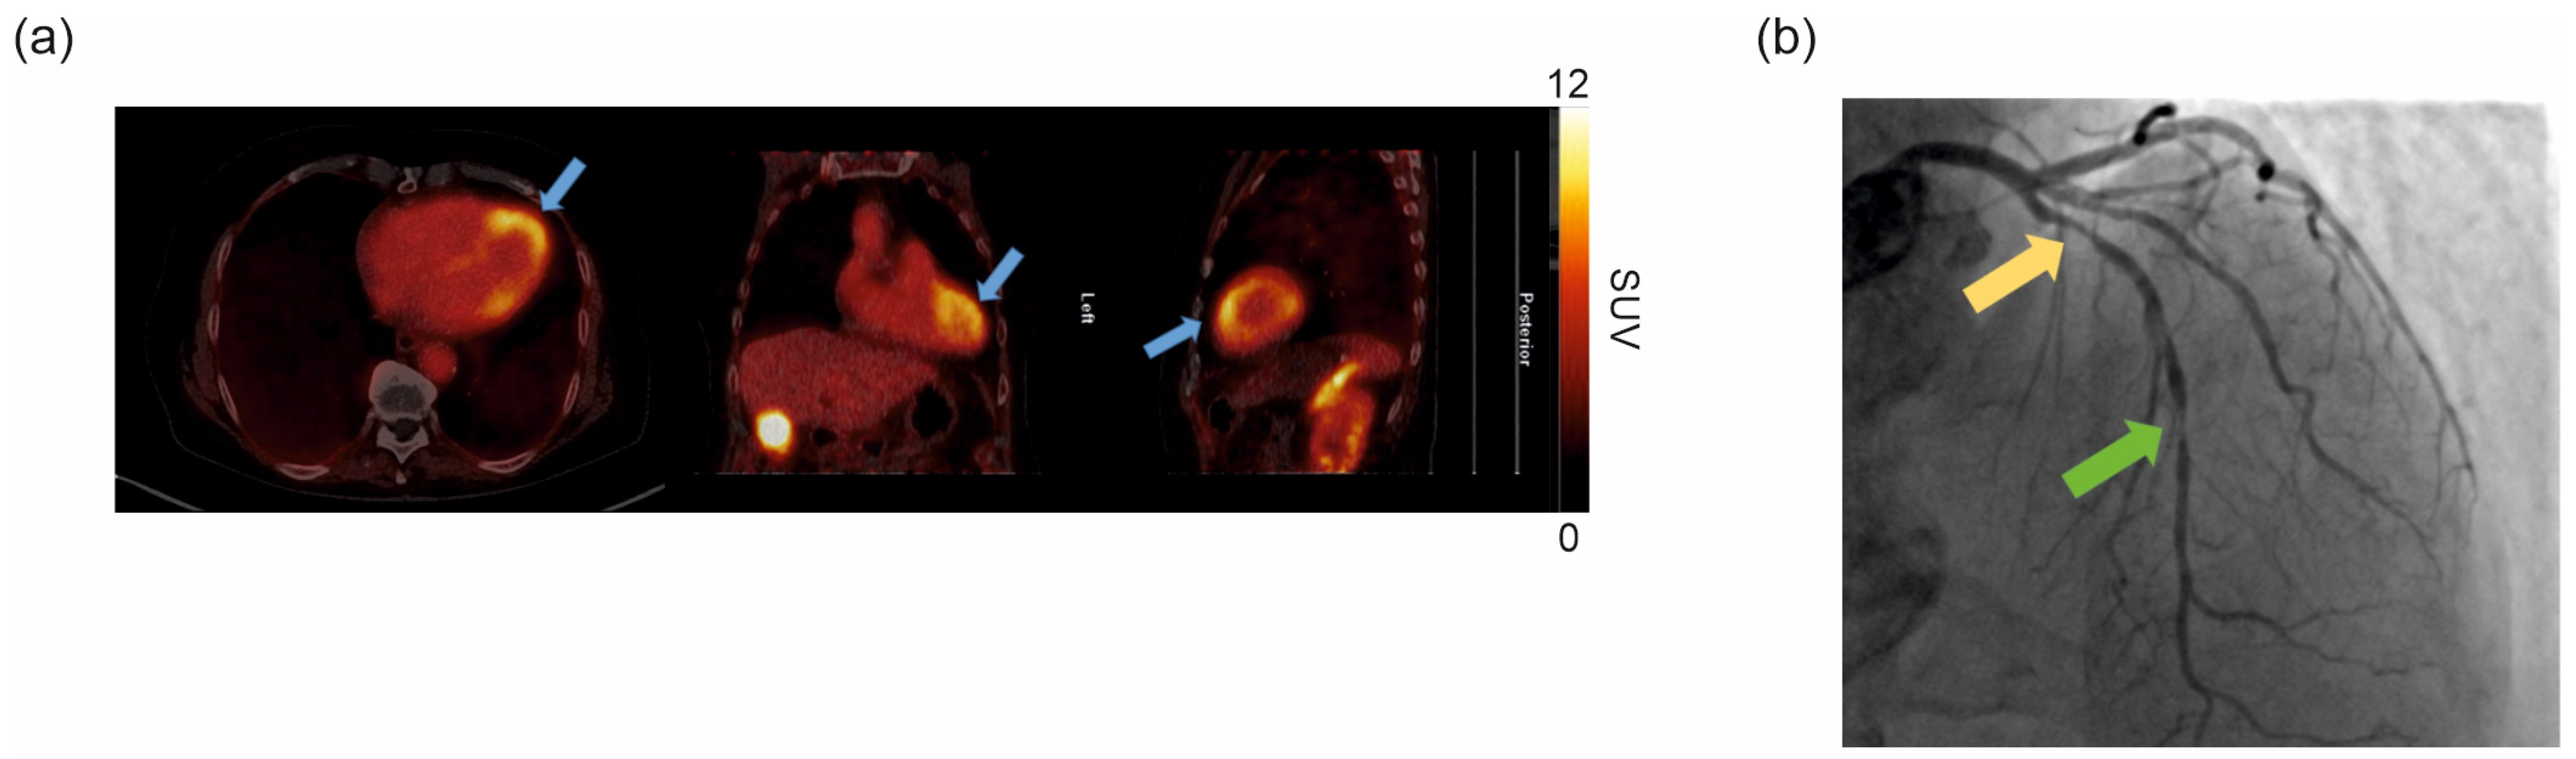

2.5. Clinical [68Ga]Ga-DATA5m.SA.FAPi PET/CT